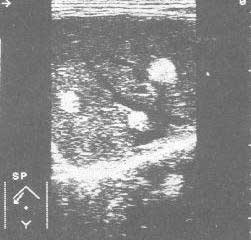

骨血管瘤檢查鼻腔可見紫紅色的新生物,瘤體質軟,多有壓縮性和推讓性,觸之易出血,但無浸潤表現。如有繼發感染,其表面糜爛、壞死和伴有息肉。若病變只限於竇內,鼻腔可無改變,故往往不易診斷。穿刺上頜竇,針管內可流出血液。X線平片檢查可能有以下幾種改變:①鼻腔及同側上頜竇及篩竇密度均勻增高,類似炎症改變;②上頜竇竇腔擴大,密度增高,類似囊腫樣改變;③竇壁骨質破壞,類似惡性腫瘤改變。血管瘤往往表現合併感染、壞死,鉗取活檢組織所見常反映不出疾病的真實情況,而且易於造成出血,但小而帶蒂的血管瘤可以一次切除,並做病理切片以確診。

鼻腔及鼻竇血管瘤的臨床表現,隨病程長短及病變範圍大小而異。鼻腔血管瘤主要為單側進行性鼻阻,如腫瘤壓迫使中隔偏曲,則有兩側鼻阻。反覆鼻出血為本病的突出表現。出血量不等,出血多者可有繼發性貧血。早期鼻竇血管瘤可無任何症狀,隨著病變增大,可出現鼻阻、鼻出血,或者血管瘤向前而由前鼻孔脫出,或向後進入鼻咽部導致咽鼓管阻塞。腫瘤較大者,竇腔擴大,骨壁受壓、吸收、變薄,甚至破壞。腫瘤向外擴展,可發生面部畸型、突眼、眼球移位、視力減退、復視、頭痛等。

根據症狀及檢查結果、性別、年齡,對典型病人多能診斷。由於此瘤極易出血,一般不做活檢。X線片及CT對腫瘤大小、擴展方向和範圍,有一定診斷價值。國外學者根據CT待檢查提出放射影象學分期:Ⅰ期,腫瘤位於鼻咽部、後鼻孔及蝶竇;Ⅱ期,腫瘤向前突入鼻腔、篩竇、上頜竇、頰及眶內側或向外擴展入翼上頜窩;Ⅲ期,腫瘤向外擴展入顳下窩及顳窩、頰、眶外側;Ⅳ期,腫瘤向顱內擴展。本病具有特徵性臨床表現,但須與鼻咽部惡性腫瘤、纖維性鼻息肉和後鼻孔息肉相鑑別。惡性腫瘤息咽表現與本病不同,腫瘤發展快,有早期頸淋巴結轉移,活檢可確診。鼻息肉質較軟,不易出血,觸診易活動,多有蒂發源於鼻腔或鼻竇。